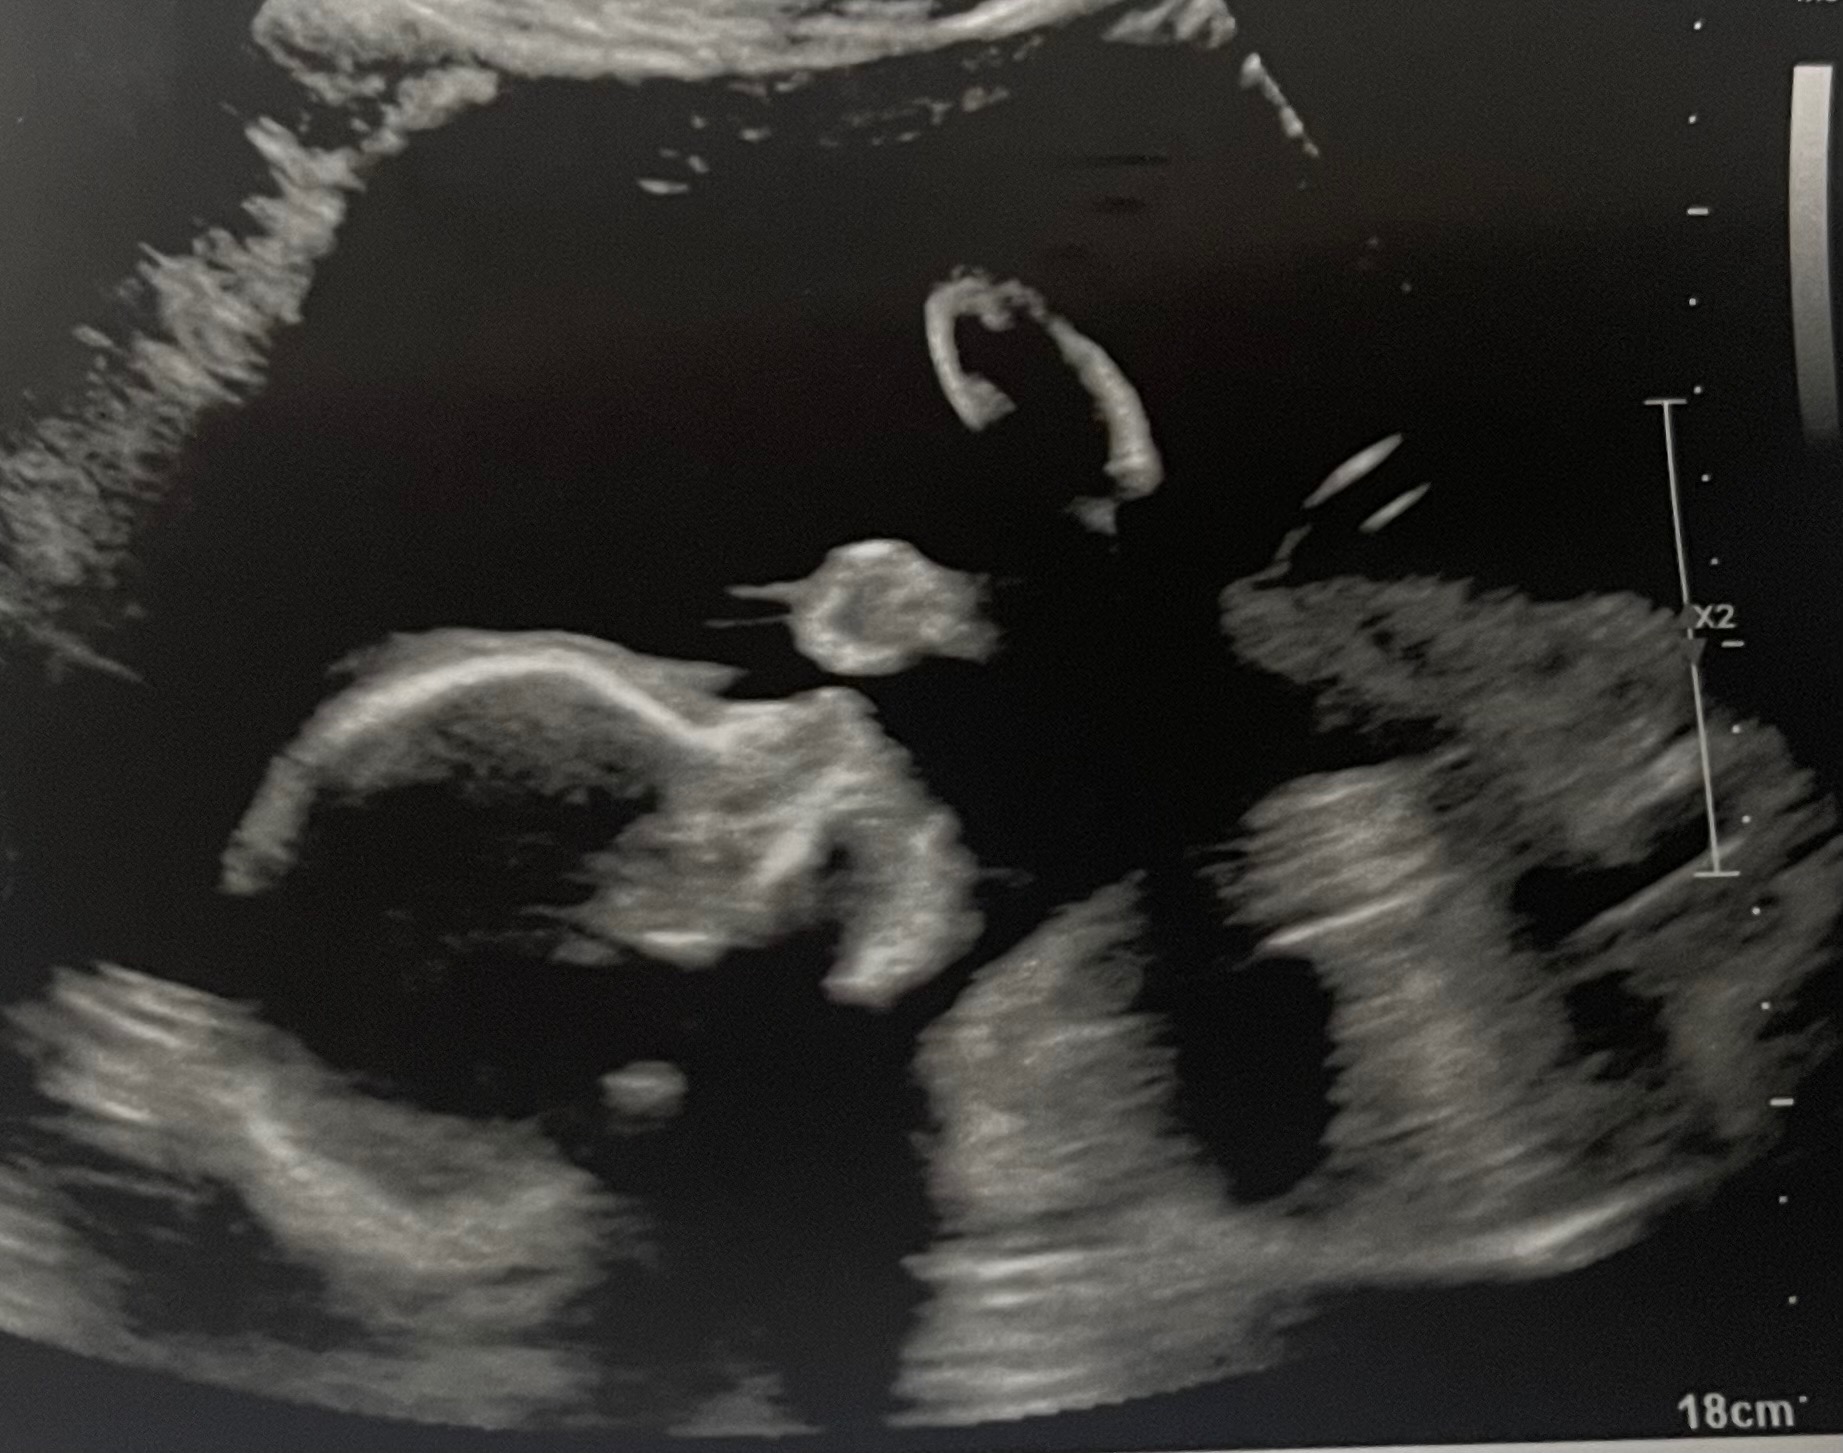

Hi, I’m Jack, and my amazing wife Alicia is now 31 weeks pregnant with our daughter, Sophia Grace. What started as a joyful ultrasound visit, so Alicia’s mom (visiting from California) could see her grandbaby, turned into an unexpected diagnosis at 27 weeks: duodenal atresia, a blockage in Sophia’s small intestine (the “double bubble” sign on MRI).

The great news? Our detailed fetal MRI at Cincinnati Children’s confirmed everything else is perfect; heart, lungs, brain, eyes, spleen, limbs, and strong growth. Genetic testing came back low risk for Down syndrome and other conditions. Sophia is a fighter, and we’re so grateful.

We’ll share updates: scans, the big move, delivery day, surgery, and Sophia’s first smiles. God has carried us every step, your prayers and shares mean the world.